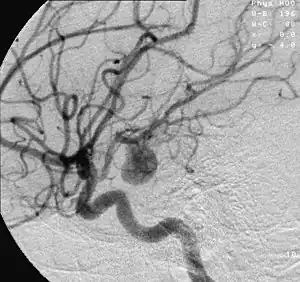

Aneurysm in a cerebral artery, one cause of hypoxic anoxic injury (HAI).

Cerebral hypoxia can be caused by any event that severely interferes with the brain's ability to receive or process oxygen. This event may be internal or external to the body. Mild and moderate forms of cerebral hypoxia may be caused by various diseases that interfere with breathing and blood oxygenation. Severe asthma and various sorts of anemia can cause some degree of diffuse cerebral hypoxia. Other causes include status epilepticus, work in nitrogen-rich environments, ascent from a deep-water dive, flying at high altitudes in an unpressurized cabin without supplemental oxygen, and intense exercise at high altitudes prior to acclimatization.